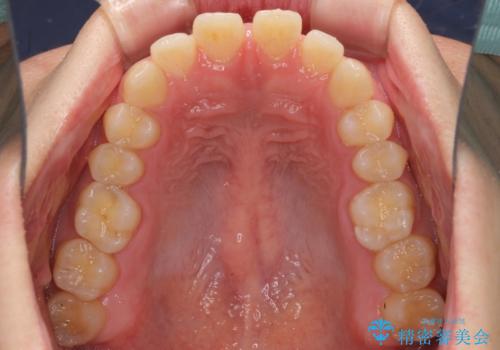

すきっ歯の改善 インビザライン矯正治療

インビザラインにより、上下の歯列を側方に拡大しつつ、前歯の隙間を閉じていくこととしました。

1日22時間の装着時間をしっかりと守ってくださったので、隙間がきれいに閉じ、口元の突出感も改善することができました。